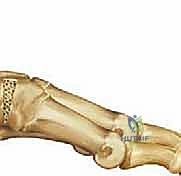

جراحة كوتون هي عبارة عن إجراء جراحي دقيق يتضمن عمل شق أو قطع في العظم الإسفيني الإنسي (Medial Cuneiform)، ثم فتح هذا الشق لتكوين فجوة على شكل "وتد" (Wedge). يتم بعد ذلك ملء هذه الفجوة بطعم عظمي (Bone Graft) وتثبيتها. النتيجة المباشرة لهذا الإجراء هي دفع مشط القدم الأول إلى الأسفل (Plantarflexion)، مما يعيد القوس الداخلي للقدم ويصحح تشوه مقدمة القدم الأروح.

3. إجراء القطع العظمي (Osteotomy)

باستخدام منشار جراحي ميكروسكوبي دقيق، يتم عمل قطع عرضي في منتصف العظم الإسفيني الإنسي. السر المهني هنا هو ترك القشرة العظمية السفلية (Plantar Cortex) سليمة دون قطعها بالكامل، لتعمل بمثابة "مفصلة" (Hinge) طبيعية تحافظ على استقرار العظم وتمنع انزلاقه.

4. فتح الوتد العظمي (Opening the Wedge)

بمجرد إجراء القطع، يتم إدخال أداة دقيقة تسمى مباعد الصفيحة (Lamina Spreader) أو أزاميل متدرجة لفتح الشق العظمي تدريجياً. يتم فتح هذا الوتد حتى يتم دفع مشط القدم الأول للأسفل ليصل إلى المستوى المطلوب (الوضع المحايد أو الانثناء الأخمصي الطفيف) مقارنة بباقي أمشاط القدم. يتم التحقق من التصحيح ميكانيكياً وبصرياً داخل غرفة العمليات.